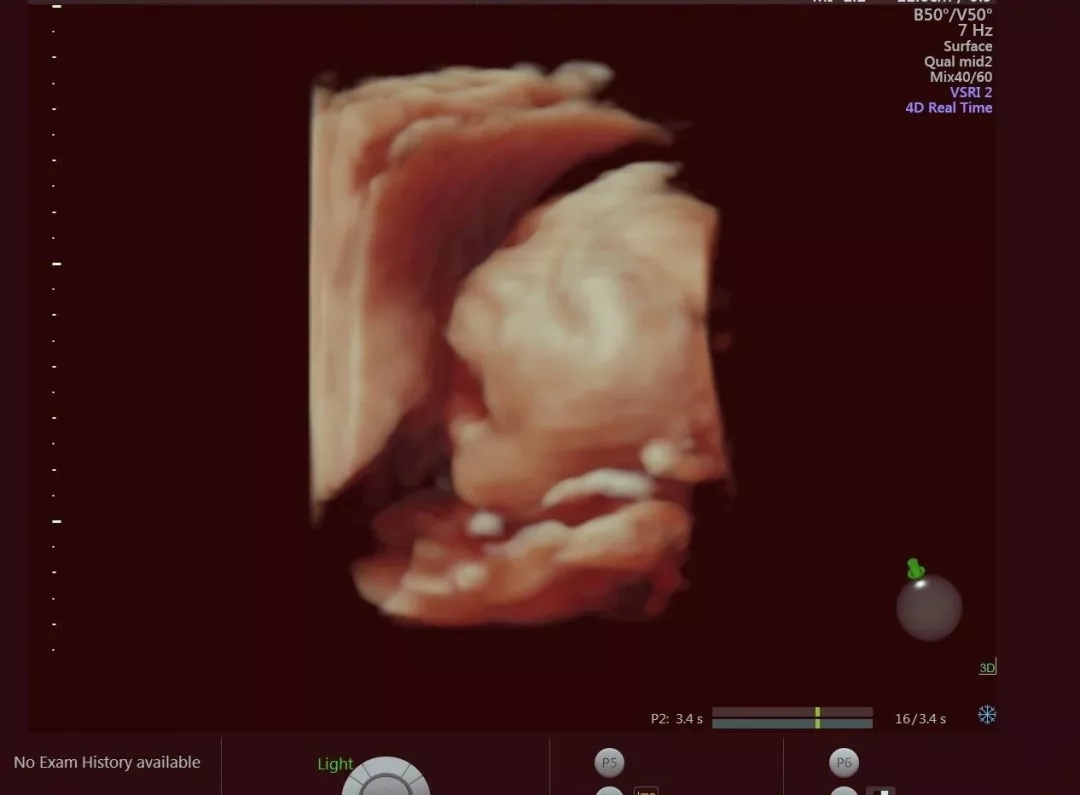

當彩超室醫(yī)生用四維彩超,

將孩子的面部表情呈現(xiàn)出來后,

李媽媽看著畫面直呼神奇!

寶寶得知有人“暗中窺探”

在媽媽肚子里,

開心的張開了小嘴,

樣子超級可愛~

四維彩超是在原先的彩超基礎上,

增加了動態(tài)的3D技術(shù),

于是原先圖片格式的寶寶,

變成了動圖格式了!